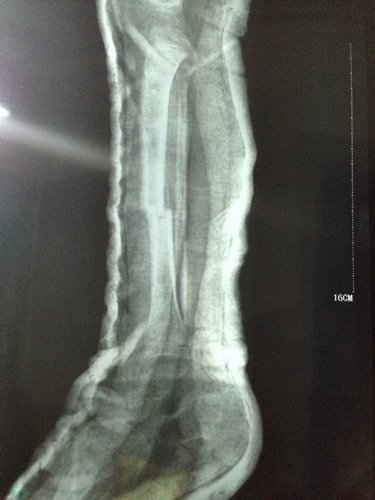

男孩三周岁 5-9 被电动车撞,右小腿胫骨骨折,正位对线良好,侧位错位三分之一。现差不多六周,前两天腿甩痛了就近急诊拍片,医生说骨头在长的,一周后把石膏拆掉吧,否则肌肉萎缩影响走路的,请各位医生指点一下,错位情况下,石膏拆了会影响恢复吗?因为两段骨头没合上阿,我上传一张之前的片子,请大家帮忙看一下。